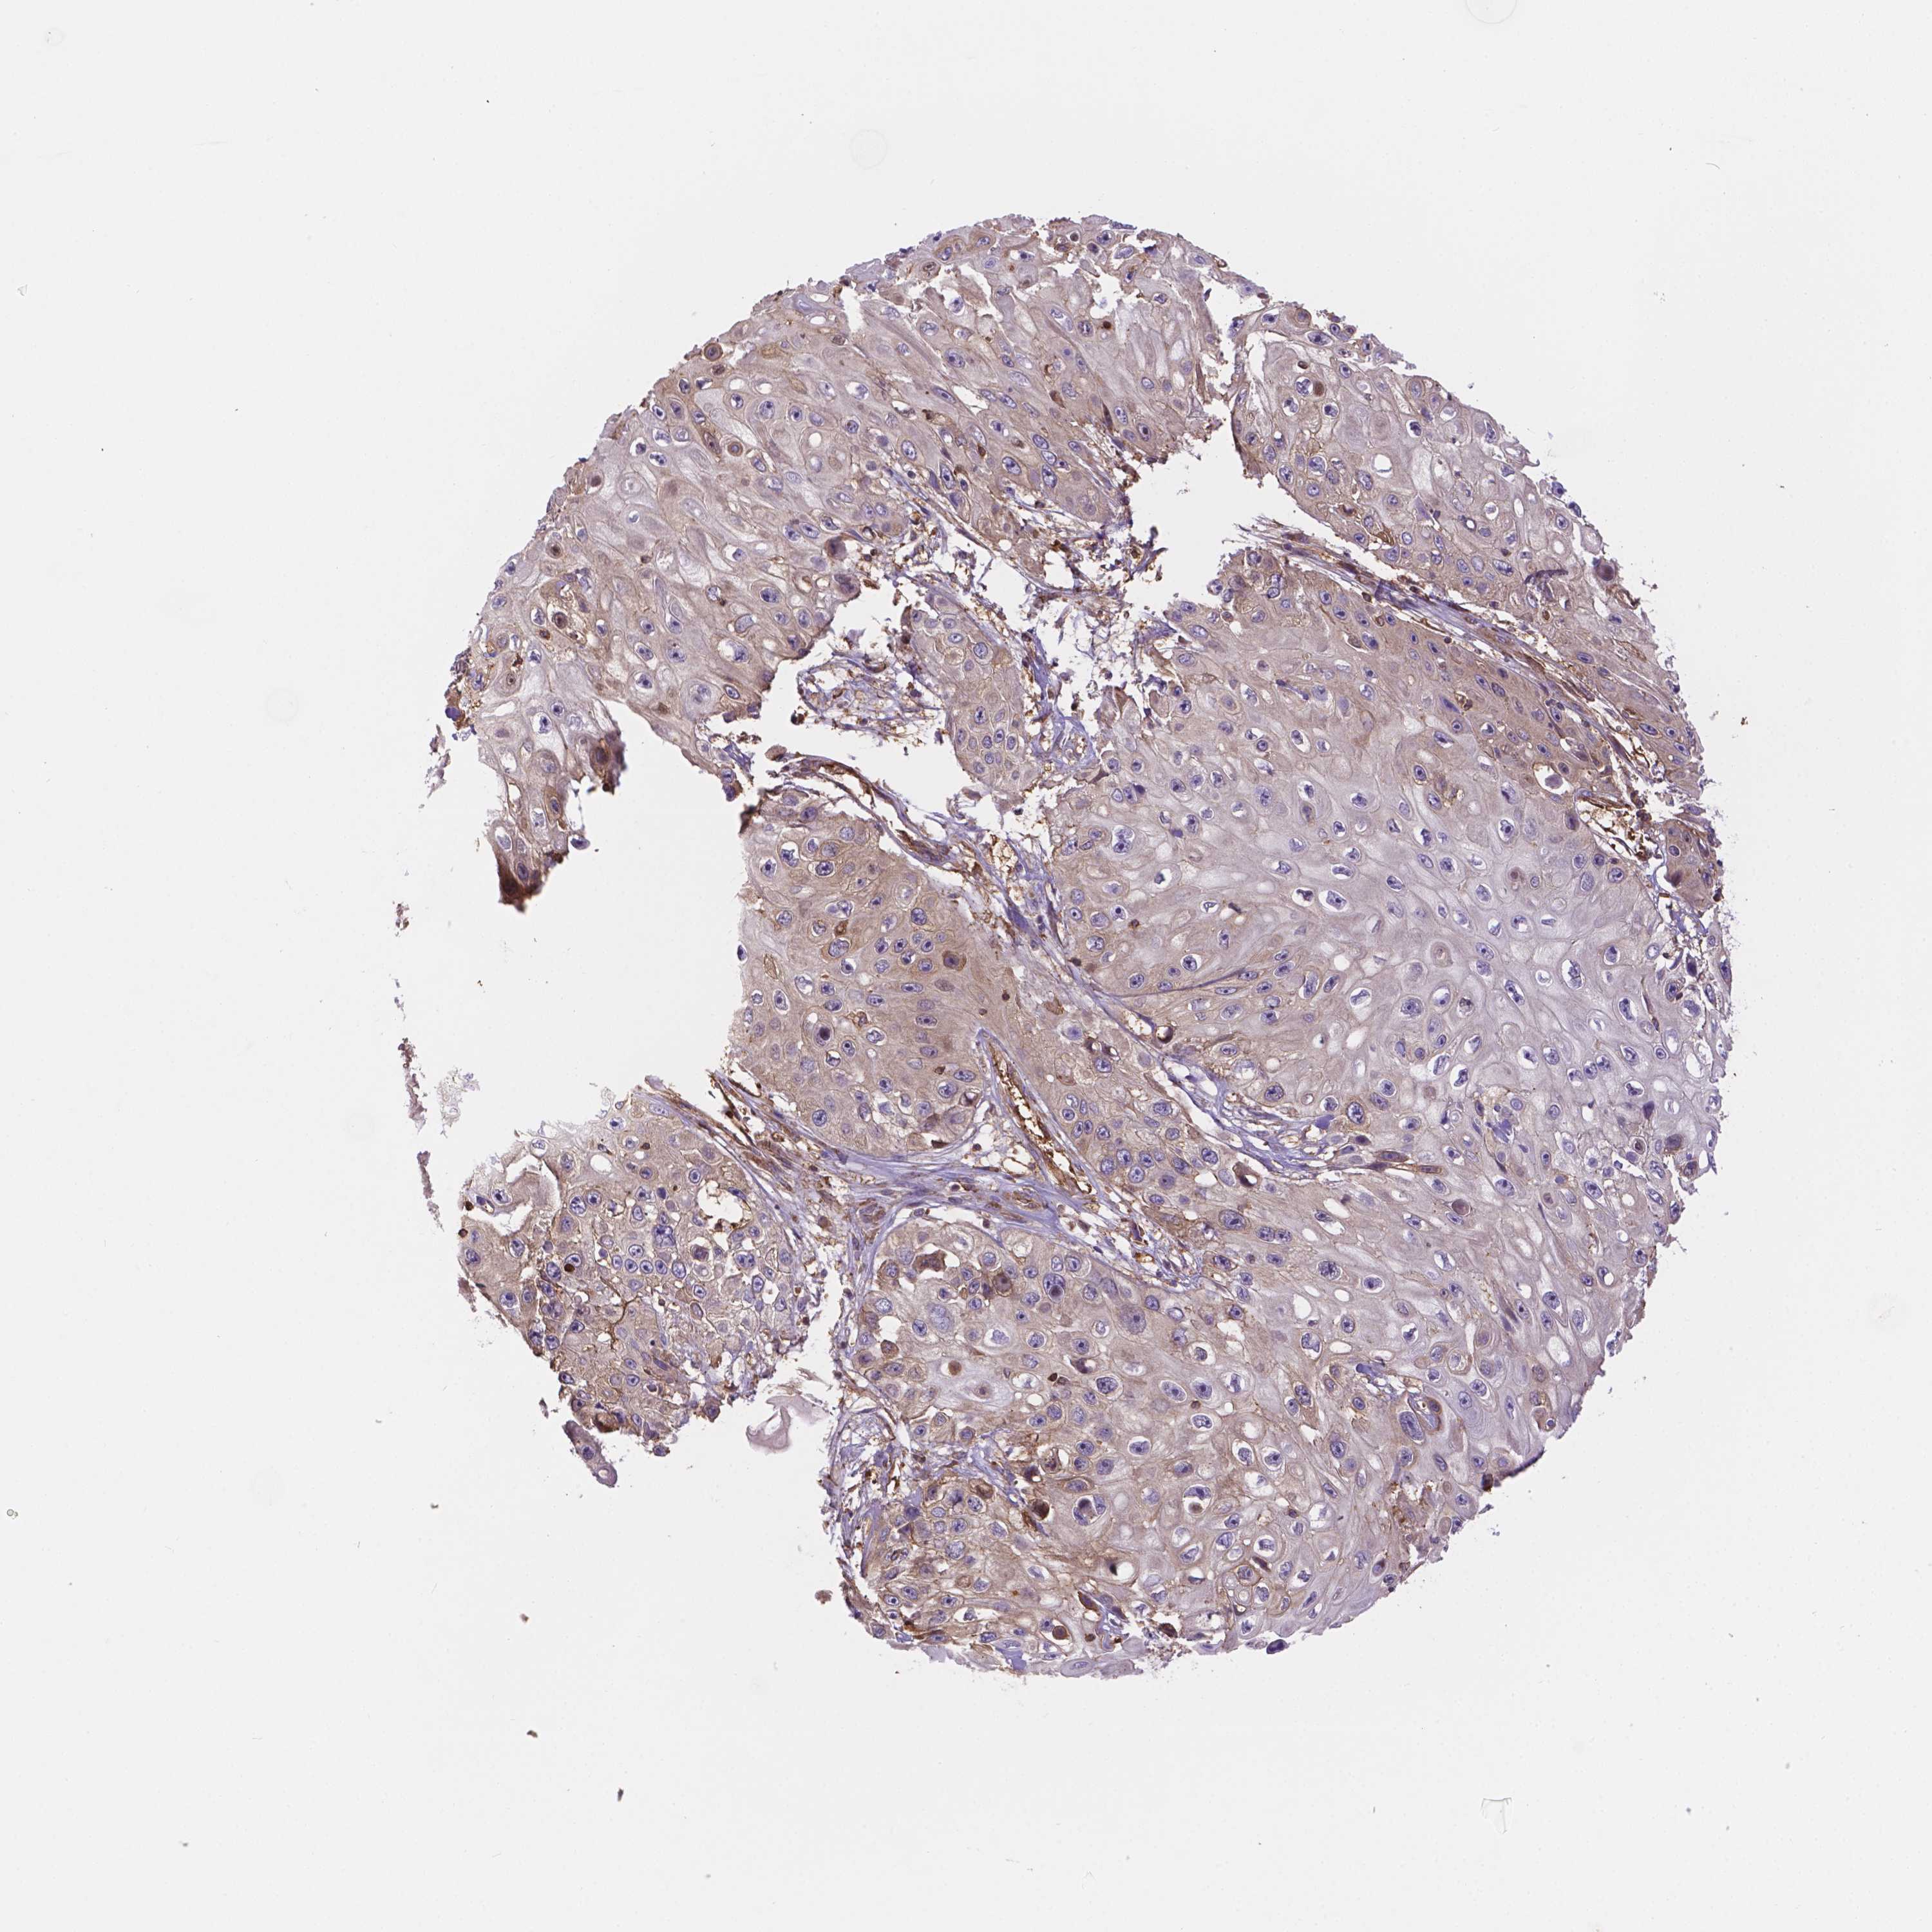

CANCER SKIN CANCER Show tissue menu

SKIN CANCER - Protein expressioni

A mouse-over function shows sample information and annotation data. Click on an image to view it in a full screen mode. Samples can be filtered based on level of antibody staining by selecting one or several of the following categories: high, medium, low and not detected. The assay and annotation is described here.

Antibody stainingi

Antibody staining in the annotated cell types in the current human tissue is reported as not detected, low, medium, or high, based on conventional immunohistochemistry profiling in selected tissues. This score is based on the combination of the staining intensity and fraction of stained cells.

Each image is clickable and will lead to virtual microscopy that enables deeper exploration of all samples and also displays staining intensity scores, fraction scores and subcellular localization as well as patient and tissue information for each sample.

Antibody HPA068172

Antibody HPA069843

Basal cell carcinoma

Squamous cell carcinoma, NOS